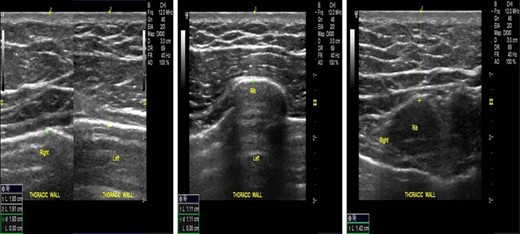

Thus, we injected a mixture of adipose-derived mesenchymal stem cells and fat transfer with (which resulted in) a post-operative period free of pain and highly satisfied aesthetic results. The patient was satisfied despite that the problem was still under correction. As presented in Fig. 2, 7 months after the second session a nearly complete symmetry was achieved. The outcome after 7 months after the second session remained inalterable after 3.5 years. No complications were noticed, and no benign growths were developed (lipomas, cysts, etc.). Furthermore, the soft tissue thoracic ultrasounds 3.5 years after the procedure (Fig. 3) showed that the lipid mass at the contraction area is like the regular one, and the patient’s satisfaction was very high. In conclusion, with the procedure that we used, we exploited to the maximum the limited adipose tissue that we had as autograft since it is known that Poland’s syndrome is characterized by fatty tissue atrophy, and our results suggests that the stem cells seems to contribute to the survival of a higher percentage of fat.

Serial soft tissue thoracic ultrasound photos 3.5 years after the first surgery indicating no pathologic findings.